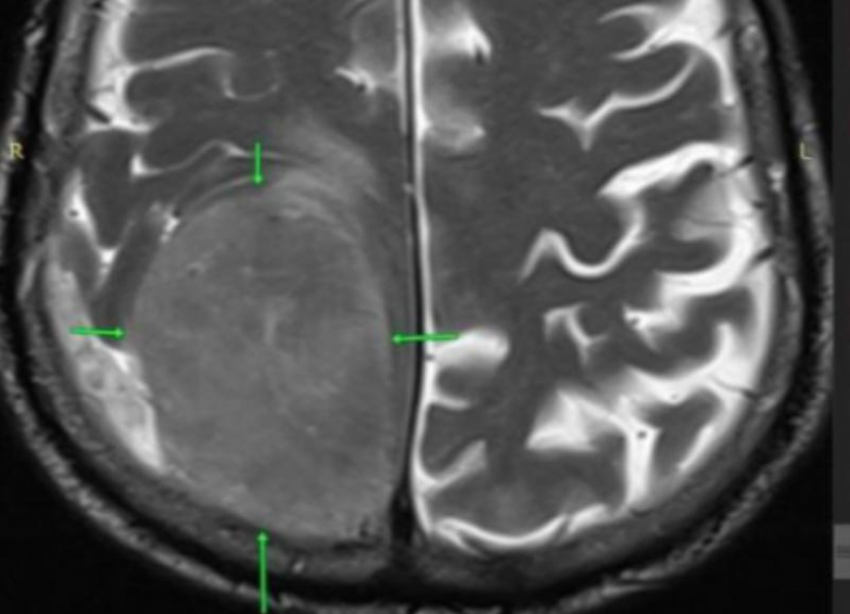

В правой теменно-затылочной области головного мозга, которая контролирует движение противоположной стороны тела, обнаружилось гигантское новообразование размером 8 на 7 сантиметров. Нейрохирурги городской клинической больницы Пятигорска провели сложнейшее вмешательство — костно-пластическую трепанацию черепа. Опухоль была полностью удалена.

Послеоперационное контрольное исследование подтвердило, что мозг восстановил свою нормальную форму, а в области вмешательства не было признаков

Состояние пациента после операции быстро улучшилось, к нему вернулась двигательная активность левой половины тела. Лабораторный анализ удаленной ткани показал, что опухоль имела доброкачественный характер.